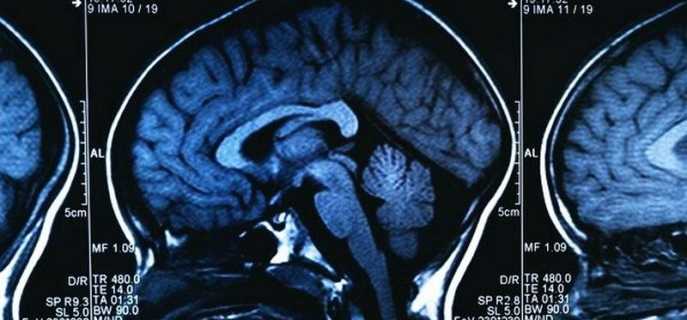

Для исследования новообразования нужно пройти следующие обследования:

- МРТ. Позволяет подробно рассмотреть новообразование, а также изучить все его особенности.